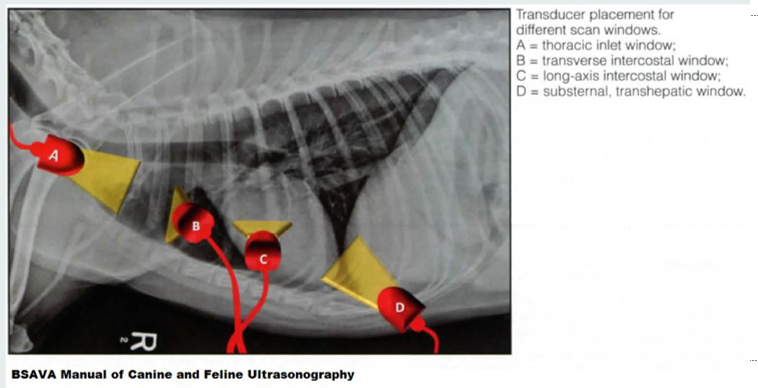

Thoracic U/S acoustic window.

thoracic inlet window

transverse intercostal window

long-axis intercostal window

substernal, transhepatic window